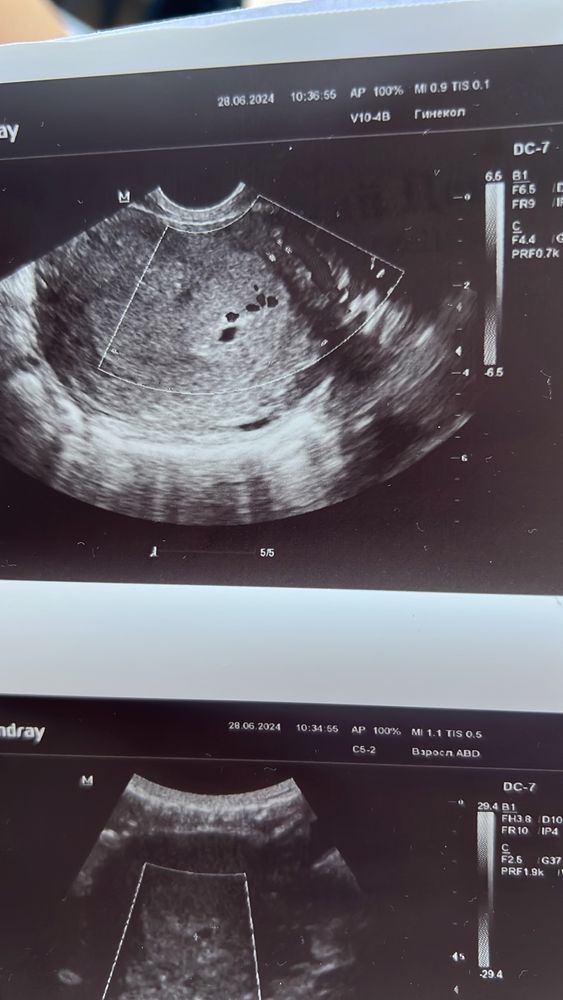

УЗИ 4-5 недель: угроза, деформация п/я, точки и кисты

Девочки, я не пойму, что на ерунда… УЗИ-стка (она же гинеколог) не внушает доверия, поставила угрозу небольшую, деформация п/я, небольшой тонус . Но в конце (меня порадовало 😂) говорит - «в целом, ничего плохого я не вижу». Выписала утрик 400 / день и хгч в динамике.

Но вопрос в другом, что с УЗИ? Что за многочисленные точки … врач предположила кисты до 5 мм, но не точно

Я бы переделала ,очень странные точки . С такими четкими границами ,может аппарат хреновый. Сходите в другую клинику через 5-6 дней)

Катюша Попова, самое главное, чтобы это не п/я в таком количестве и не опухоль какая-то 😀

Возможно полипы или миомы,типо что-то этого. Дайте фото распечатки УЗИ,там все написано.